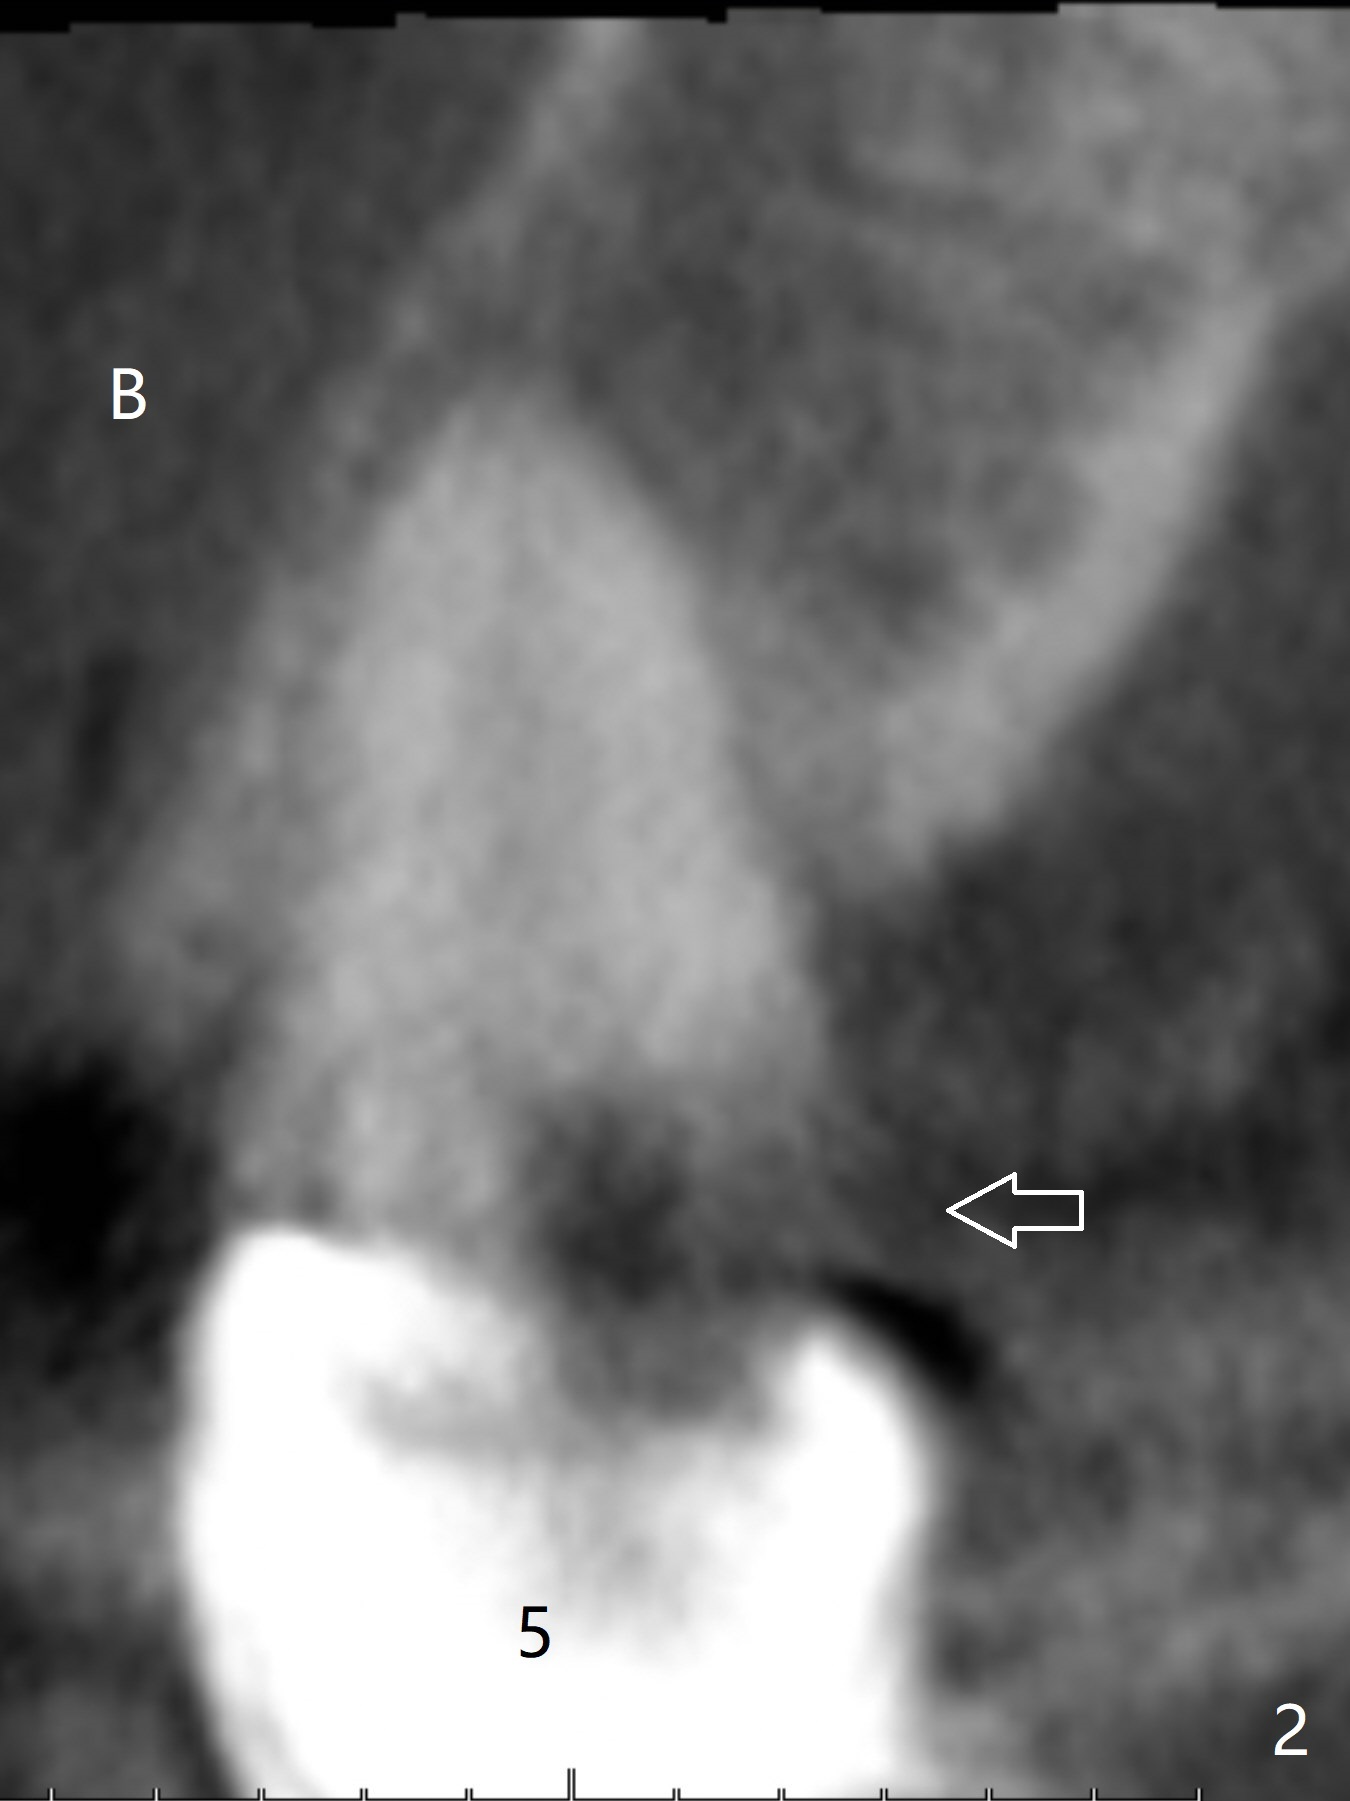

A 43-year-old woman has a failing upper right bridge (Fig.1: #2-5). While the abutment at #5 has apparently palatal open margin (Fig.2,3) and that at #4 has severe palatal bone loss (Fig.4 arrow), that at #2 has the poorest prognosis (Fig.6,7). Panoramic X-ray or PAs will be taken because of CBCT cone cut when the patient returns for #30 and 31 post-implant follow-up. Alginate impression will be taken for the upper right quadrant for provisional. The bridge will be sectioned between #3 and 5 (Fig.1 red lines) to determine salvageability of the abutments at # 4 and 5. If the latter are ok, the abutment at #2 will be extracted (expected to be loose) and implants will be placed at #2 and 3. If #4 is bad while #5 is ok, the former will be extracted and implants will be placed at #2 and 4 with a bridge. If #5 is bad while #4 is ok, implants will be placed at #2, 3 and 5.